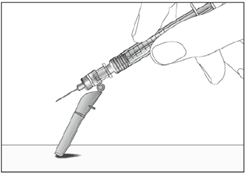

8. Drücken Sie das Schutzschild in Richtung Nadel (siehe Abbildung 11).

9. Positionieren Sie das Schutzschild im Winkel von ca. 45° auf einer ebenen Fläche (siehe Abbildung 12).

10. Drücken Sie die Nadel mit einer kräftigen, schnellen Bewegung nach unten, bis deutlich ein Klicken zu hören ist (siehe Abbildung 13).

11. Stellen Sie visuell sicher, dass die Nadel vollständig unter der Sperre im Schutzschild eingerastet ist (siehe Abbildung 14).